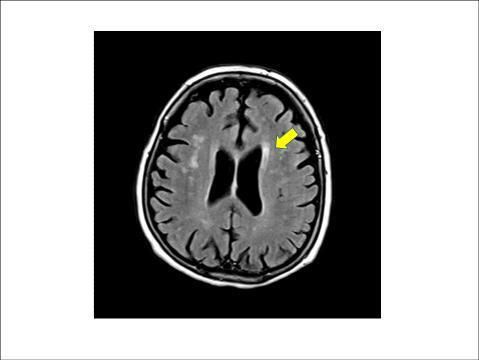

연구팀은 분석 대상자의 거주지역별 연평균 미세먼지 농도를 연간 노출량으로 추정하고 1년간의 노출량 차이가 '뇌 백질 변성'(WMH), '무증상(열공성) 뇌경색', '뇌 미세출혈' 등의 병변과 어떤 연관성이 있는지를 분석했다. 조사 기간 중 전체 지역의 미세먼지 평균 농도는 49.1㎍/㎥이었다.

뇌 백질은 MRI 영상에서 뇌 중심부 옆으로 하얗게 보이는 부분을 말하는데, 이 백질에 퍼져 있는 작은 혈관들이 손상된 상태를 뇌 백질 변성이라고 한다. 또 무증상 뇌경색은 뇌 속 작은 혈관이 막혀 생기는 질환을 일컫는다.

이들 질환 모두 MRI에서 무증상의 병변으로 보이지만, 점차 뇌 노화가 비정상적으로 진행되면서 뇌졸중이나 치매 등 심각한 질환으로 이어질 수 있다.

연구팀은 미세먼지 농도가 10㎍/㎥ 증가할 때마다 뇌 백질 변성 면적이 약 8%씩 증가하는 것으로 추산했다. 또 같은 조건에서 무증상 뇌경색이 발생할 위험은 약 20% 더 높아지는 것으로 평가했다.